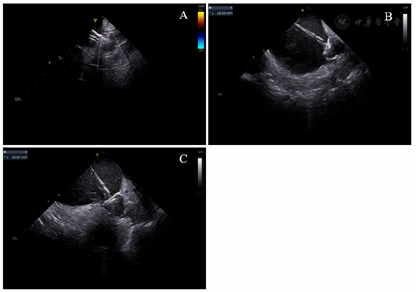

在局部麻醉下穿刺双侧股静脉,经左侧股静脉通路置入6 F静脉血管鞘,沿鞘送入10级可调弯冠状窦电极,经右股静脉通路分别置入2根8.5 F Swartz长鞘,使用Brockenbrough针行两次房间隔穿刺。静脉注射肝素,使ACT维持在300~350 s。在导丝引导下将Swartz鞘送入左房,撤出导丝和Brockenbrough针,经Swartz鞘分别放入Lasso环状标测电极(美国强生公司)和Smarttouch压力消融导管(美国强生公司)。在Carto 3D三维标测系统(美国强生公司)指导下,使用Lasso电极构建左房和肺静脉的三维解剖模型,放置Lasso电极于左右肺静脉口部,消融电极沿左右肺静脉行环肺静脉电隔离,终点为肺静脉内与左心房传导双向阻滞。消融后患者心律仍为房颤心率,给予双向150 J同步直流电复律后转为窦性心律。观察20分钟,反复心房程序刺激未诱发房性心动过速,再次验证四支肺静脉电位未恢复,房颤消融手术成功。撤出Lasso电极,换11 F鞘管,将ICE电极经鞘管送入左房,分别以45°、90°和135°测量左心耳口部直径分别为20.77、20.62、20.19 mm,深度为24.23、25.28、24.37 mm(图1)。与术前经食道超声所测的左心耳大小数据相似度较高。留置导丝至左上肺静脉,退出鞘管,经导丝送入14 F Watchman输送鞘至左心房,经鞘管和导丝送入5 F猪尾导管至左房,退出导丝调整猪尾导管至左心耳,右前斜30°、足位20°造影显示左心耳形态为单分叶风向袋型,测量口部直径为21.62 mm,深度为24.83 mm,推送鞘管至左心耳内,退出猪尾导管,经鞘管推送27 mm的Watchman(美国波士顿科学)封堵器至左心耳,经X线核实位置后,缓慢释放封堵器,X线造影和ICE核实封堵器位置良好,45°、90°和135°测量均无残余分流、无露肩(图2),压缩比分别为20%、22%、20%。封堵器牵拉试验未见移位及脱落,逆时针旋转输送器并释放封堵器。观察10 min,ICE复查封堵器位置,再次测量残余分流、露肩和压缩比,与释放前相比各角度均无明显变化(图3)。术中ICE测量无嵴水肿、无心耳旁积液、无心包积液,左心耳封堵手术成功。房颤导管消融及左心耳封堵手术时间为103 min,透视剂量为356 mGy。